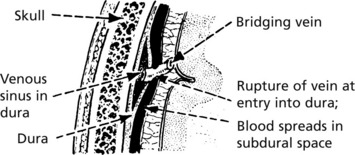

late sign of increased intracranial pressure